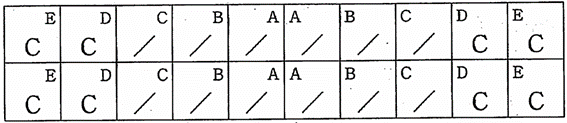

母子保健法に基づく3議児歯科健康診査の結果の一部を図に示す。う蝕罹患型はどれか。1つ選べ。

a. A型

b. B型

c. C1型

d. C2型

解答を見る

a